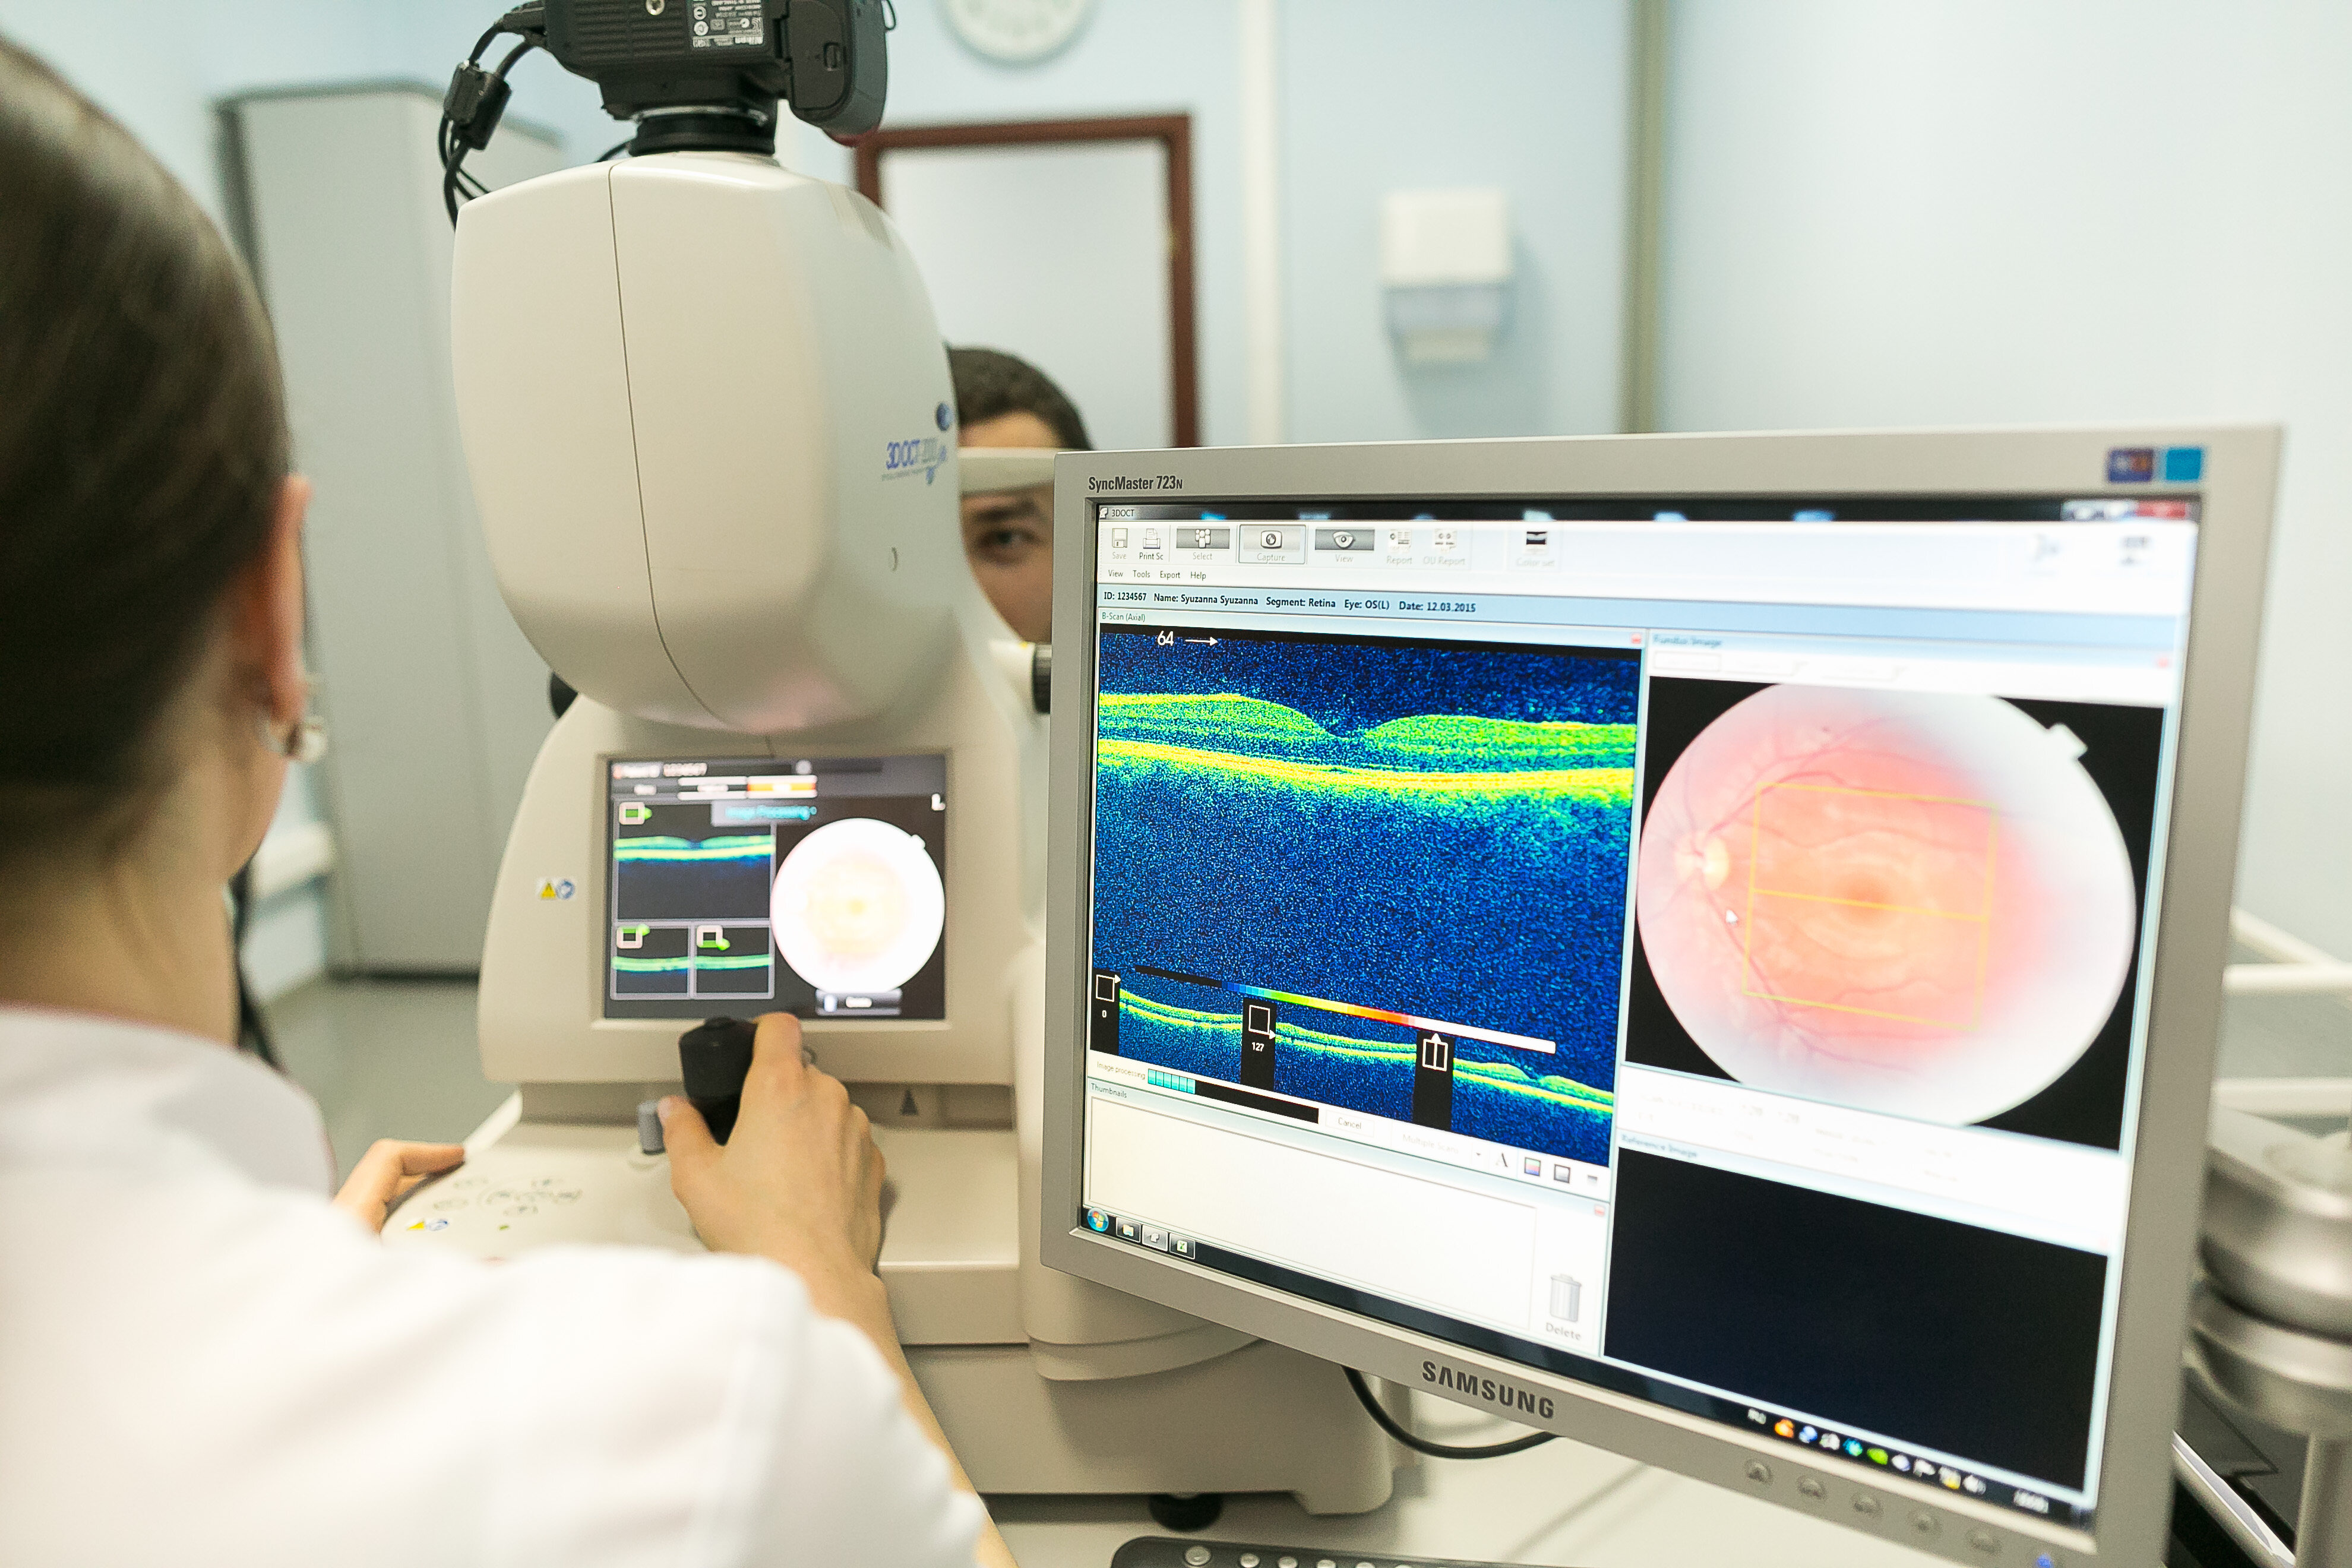

Диагностика зрения: Когерентная томография сетчатки

Раздел: Фотоальбом решений